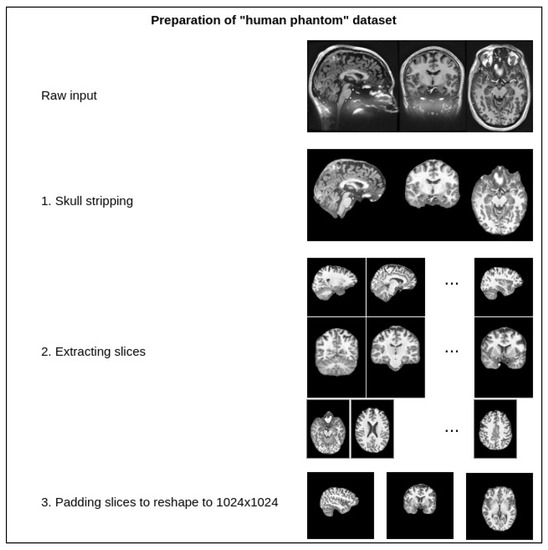

4.1. Experimentation Data